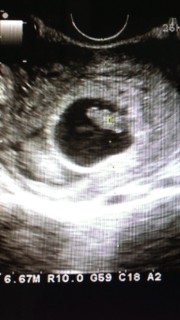

CRL:13.5mm

前回から2週間ぶりの検診でした。 途中で痛みがあったり出血も少しありましたが、 問題なく育っていて一安心です♡

二等身になり人形になっていたので 更に可愛く思えます。 このまま元気に育ってね(^^) 次回は母子手帳も貰える予定です。 CRL13.6mm

二回目の検診で2週間ぶり!

大きくなって手足も

見え始めました。